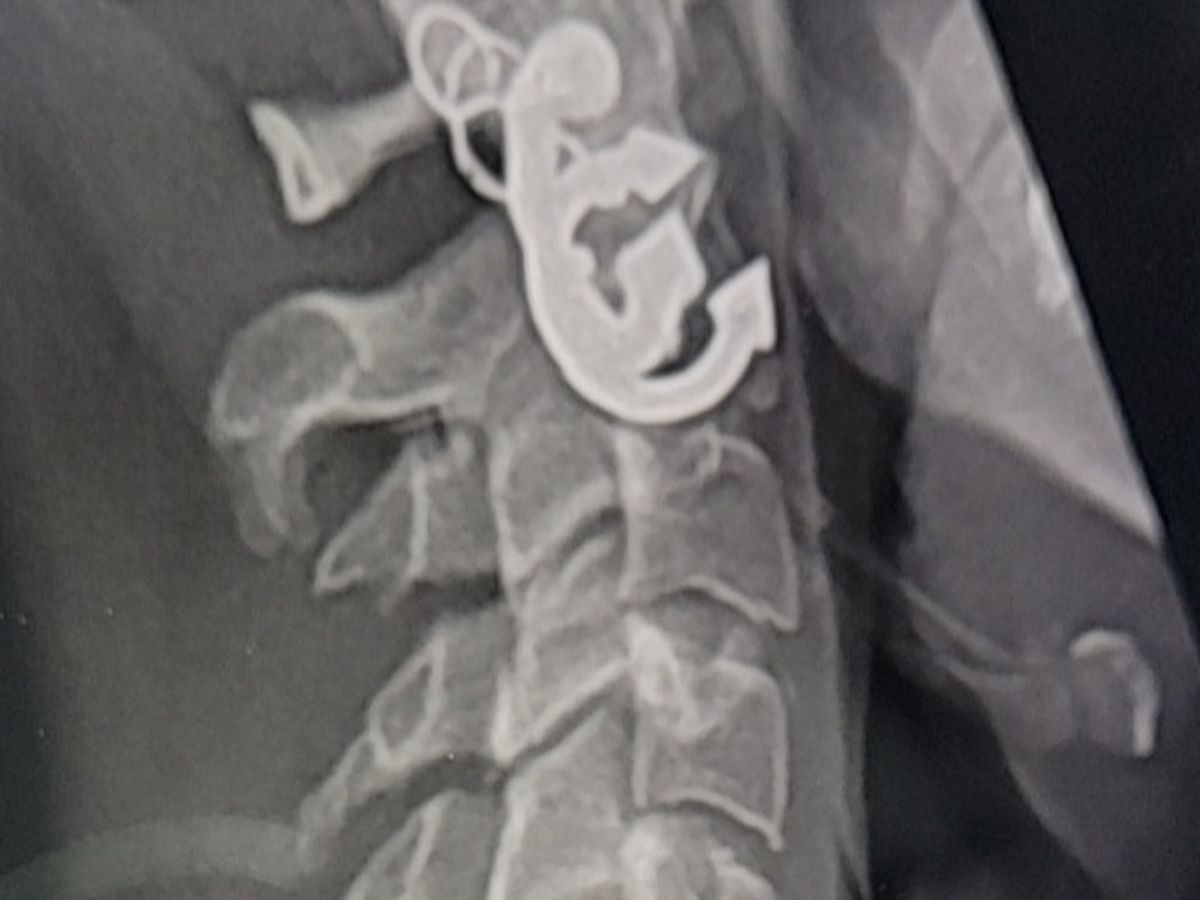

Hello, my name is Haley : )) I'm close to getting my hearing date for my year-long fight for disability. I have marfans syndrome causing many past foot/knee injuries and scoliosis. I have a good job that I work part-time but it affects my body in a way that any standing up n moving job would. After work I have to lay down on something soft and flat to get rid of the pain, it sorta feels like the tendons are out of place beforehand. My bed is not flat, was on my way to pick up a mattress when my cars engine blew out. I'm a little scared to doordash in my rental but If I'm feeling able some point after work I have to try. January was the winter slump, I had two hours a week and was extra immobile from a rotation in my neck. Had to use that check for a chiropractor 3 times and he definitely made the pinching go away but I need to see him again soon, might fix the current back-shoulder-hand issues. Not sure when my rental company would serve an eviction notice but my options have been an unrewarding journey, hoping to win my case and pay back anyone willing to help.